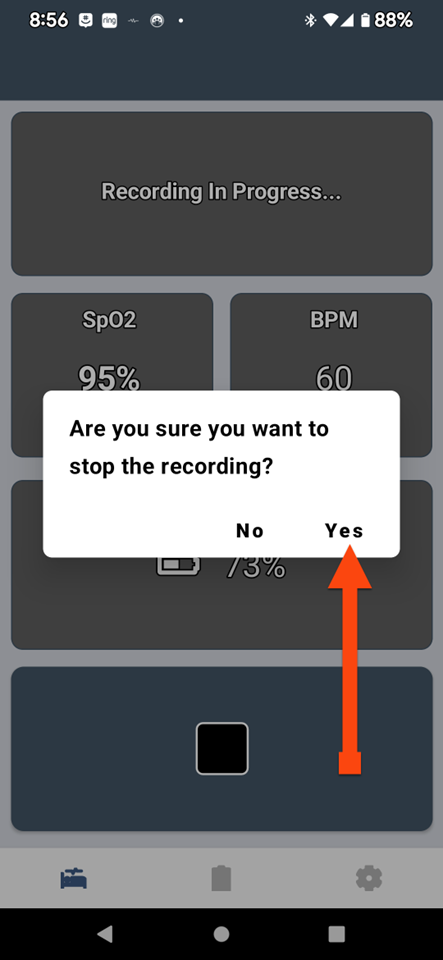

SLEEPIMAGE APP (Android)

SLEEPIMAGE APP (Android)

SLEEPIMAGE APP (Android)

SLEEPIMAGE APP (Android)

SLEEPIMAGE APP (Android)

SLEEPIMAGE APP (Android)

SLEEPIMAGE APP (Android)

SLEEPIMAGE APP (Android)

SLEEPIMAGE APP (Android)

SLEEPIMAGE APP (Android)

SLEEPIMAGE APP (Android)

SLEEPIMAGE APP (Android)

SLEEPIMAGE APP (Android)

SLEEPIMAGE APP (Android)

SLEEPIMAGE APP (Android)

SLEEPIMAGE APP (Android)

SLEEPIMAGE APP (Android)

SLEEPIMAGE APP (Android)

SLEEPIMAGE APP (Android)

SLEEPIMAGE APP (Android)